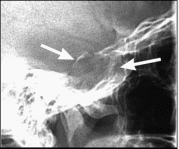

Рентгенологическими признаками аденомы гипофиза являются изменение формы и размеров турецкого седла, истончение и деструкция костных структур, образующих его.

Рисунок Прицельная рентгенограмма турецкого седла. Макроаденома гипофиза. Увеличение размеров турецкого седла (стрелки) и разрушение нижней стенки.